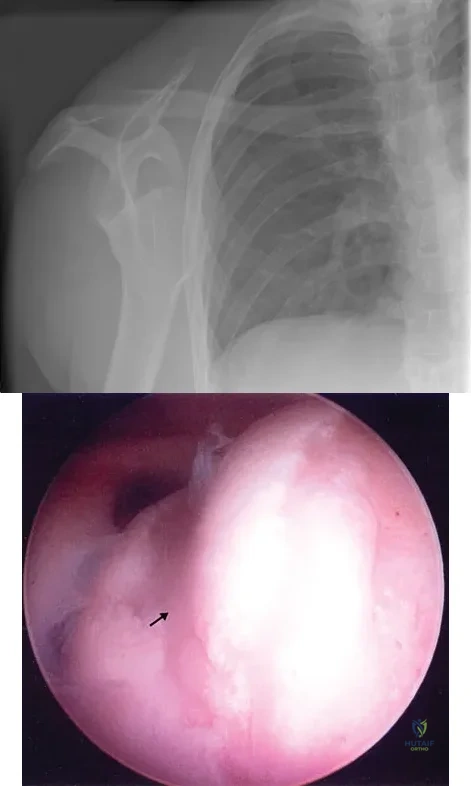

Figure 4a shows the radiograph of a 20-year-old man who has an injury to the right shoulder. Figure 4b shows an arthroscopic view (posterior portal). The arrow points to a

Explanation